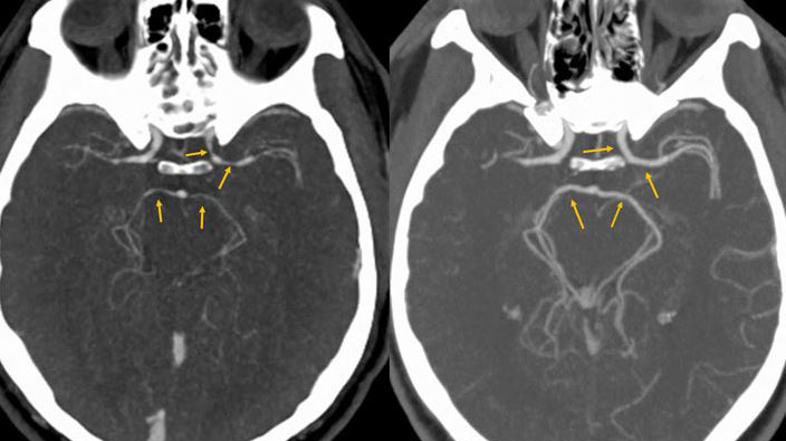

Računalniška tomografija glave pokazala, da so se moškemu močno zožile arterije.

Prvi pregledi niso odkrili ničesar nenavadnega. Računalniška tomografija glave pa je pokazala, da so se moškemu močno zožile arterije. Po zdravljenju, ki je vključevalo hidratacijo in uživanje protibolečinskih tablet, so se glavoboli končali. Pet dni kasneje so slike možganov pokazala, da so arterije vrnile v običajno velikost.